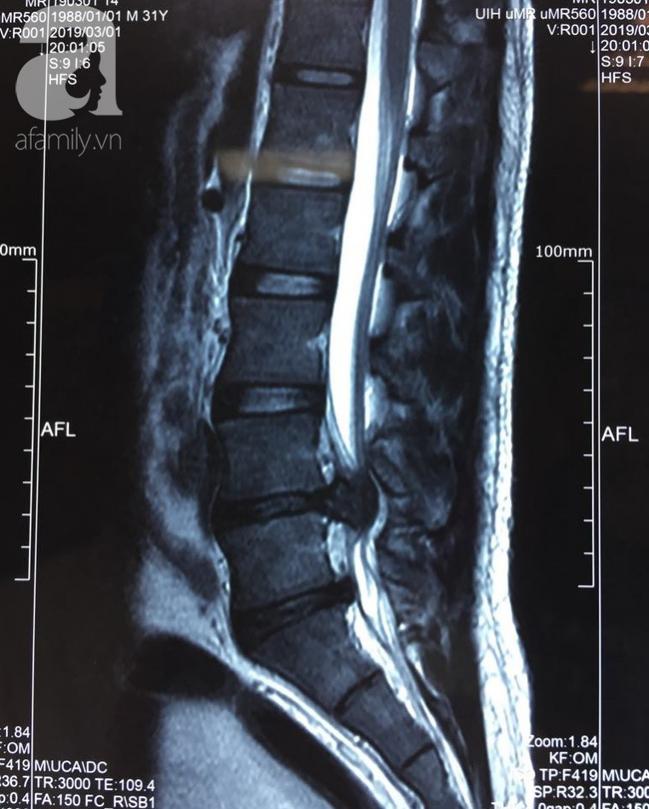

Tại bệnh viện sau khi tiến hành thăm khám và thực hiện chụp MRI cột sống thắt lưng, các bác sĩ phát hiện bệnh nhân bị thoát vị đĩa đệm tầng L4-L5 dạng mảnh rời, xuyên dây chằng dạng trung tâm – cạnh trung tâm bên trái, kích thước khoảng 16mm. Điều này gây ép bao màng cứng, chèn ép mạnh các rễ thần kinh.

Ảnh chụp MRI cột sống lưng của bệnh nhân.

Bác sĩ Huỳnh Hồng Châu, Trưởng khoa Ngoại Thần kinh của một bệnh viện cho biết, bệnh nhân V. thoát vị đĩa đệm cấp với khối mảnh rời lớn, chèn ép chùm rễ thần kinh đuôi ngựa. Tình trạng này cần phải mổ cấp cứu trong thời gian 24 giờ kể từ lúc yếu liệt chân với hy vọng phục hồi cơ vòng 52%.